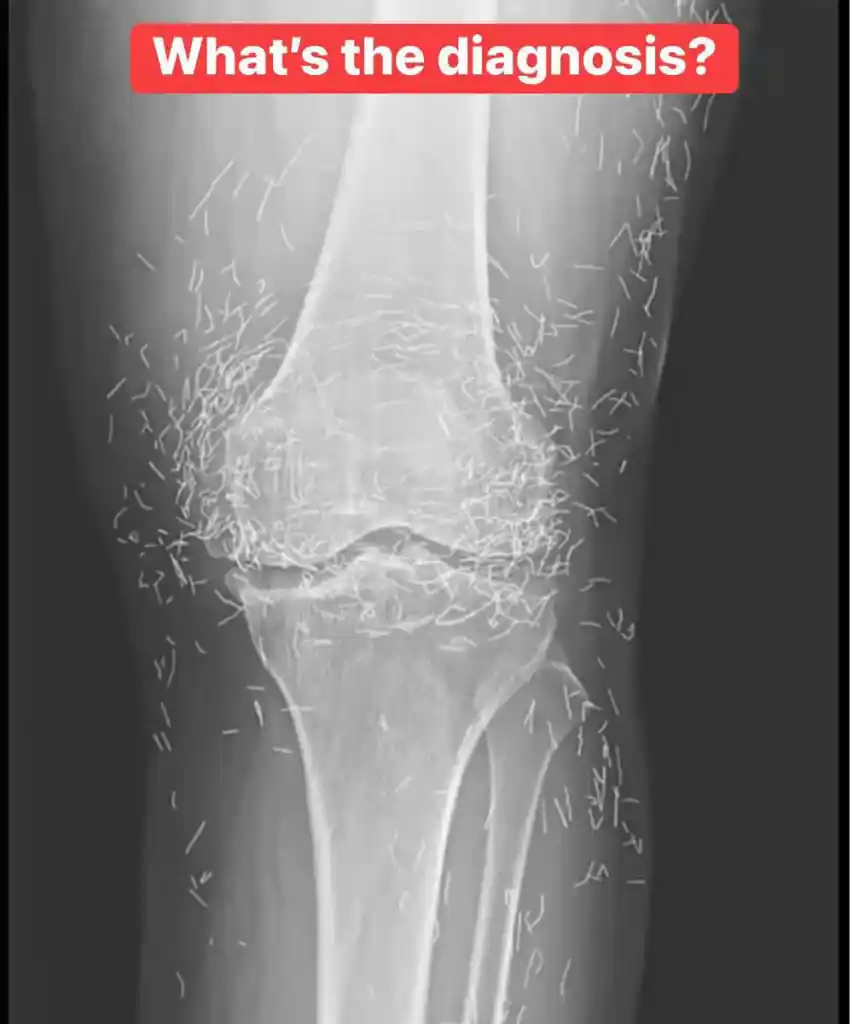

Doctors were recently surprised by an X-ray image of a 65-year-old woman’s knees. The scan showed not just bone, but hundreds of tiny gold needles embedded deep within the tissue. The woman, from South Korea, had been suffering from osteoarthritis, a painful condition where the joints wear down. When traditional pain medications failed to help and caused stomach issues, she turned to an alternative treatment: acupuncture.

In this specific case, her acupuncturist had used gold needles and intentionally left them inside her knees. The goal of this unusual method was to provide continuous stimulation to the joints in an attempt to relieve her chronic pain. While this practice is known in some parts of the world, it is highly unusual and caught her new doctors off guard. Medical experts not involved in her care have pointed out the significant risks of leaving any foreign object inside the body long-term.

These risks include the potential for inflammation, infection, and the formation of painful abscesses. The needles can also interfere with important medical scans, potentially blocking the view of anatomy on an X-ray. Furthermore, a patient with metal needles inside them cannot safely undergo an MRI scan, as the powerful magnets could cause the needles to move, potentially damaging blood vessels or tissue. While acupuncture remains a popular treatment for joint pain, there is limited scientific evidence to prove its effectiveness, and this extreme version of the practice highlights the potential dangers of alternative therapies.